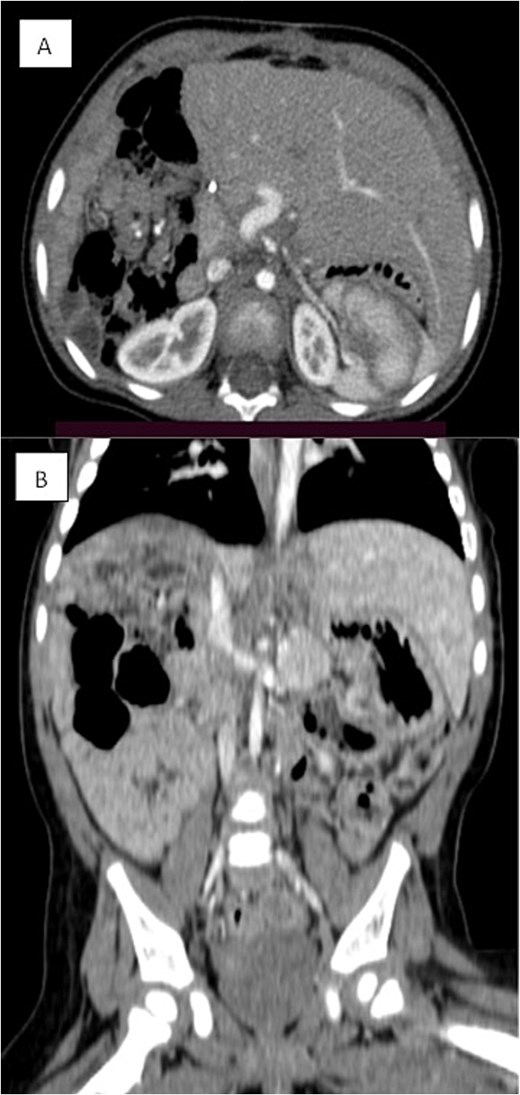

Several months later, she developed progressive abdominal distension and recurrent vomiting, prompting further evaluation. A CT scan of the abdomen revealed a large heterogeneous hepatic mass primarily occupying the right lobe, measuring 12.6 × 8.8 × 14 cm, with multicystic areas and soft tissue enhancement. MRI also demonstrated a large right hepatic lobe mass with mass effect and heterogeneous enhancement (Figs 1 and 2). Mild upper abdominal lymphadenopathy was noted (largest node 8 × 10 mm), along with a right-sided inguinal hernia. Differential diagnoses included HMH, with hepatoblastoma and undifferentiated sarcoma considered less likely. A chest CT showed mild pericardial effusion and an inflammatory appearance.

Coronal MRI images of the abdomen showing a mass effect in the right hepatic lobe. (A) Coronal T1 post-contrast and (B) coronal T2 HASTE FS images demonstrate spatial relationships, including compression of the right kidney, pancreas, and major vessels, with no invasion. The mass displaces bowel loops inferiorly and causes an anterior abdominal wall bulge.